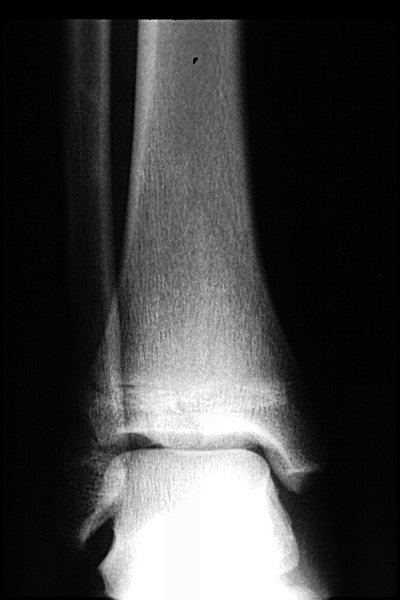

Return to Triplane Fracture